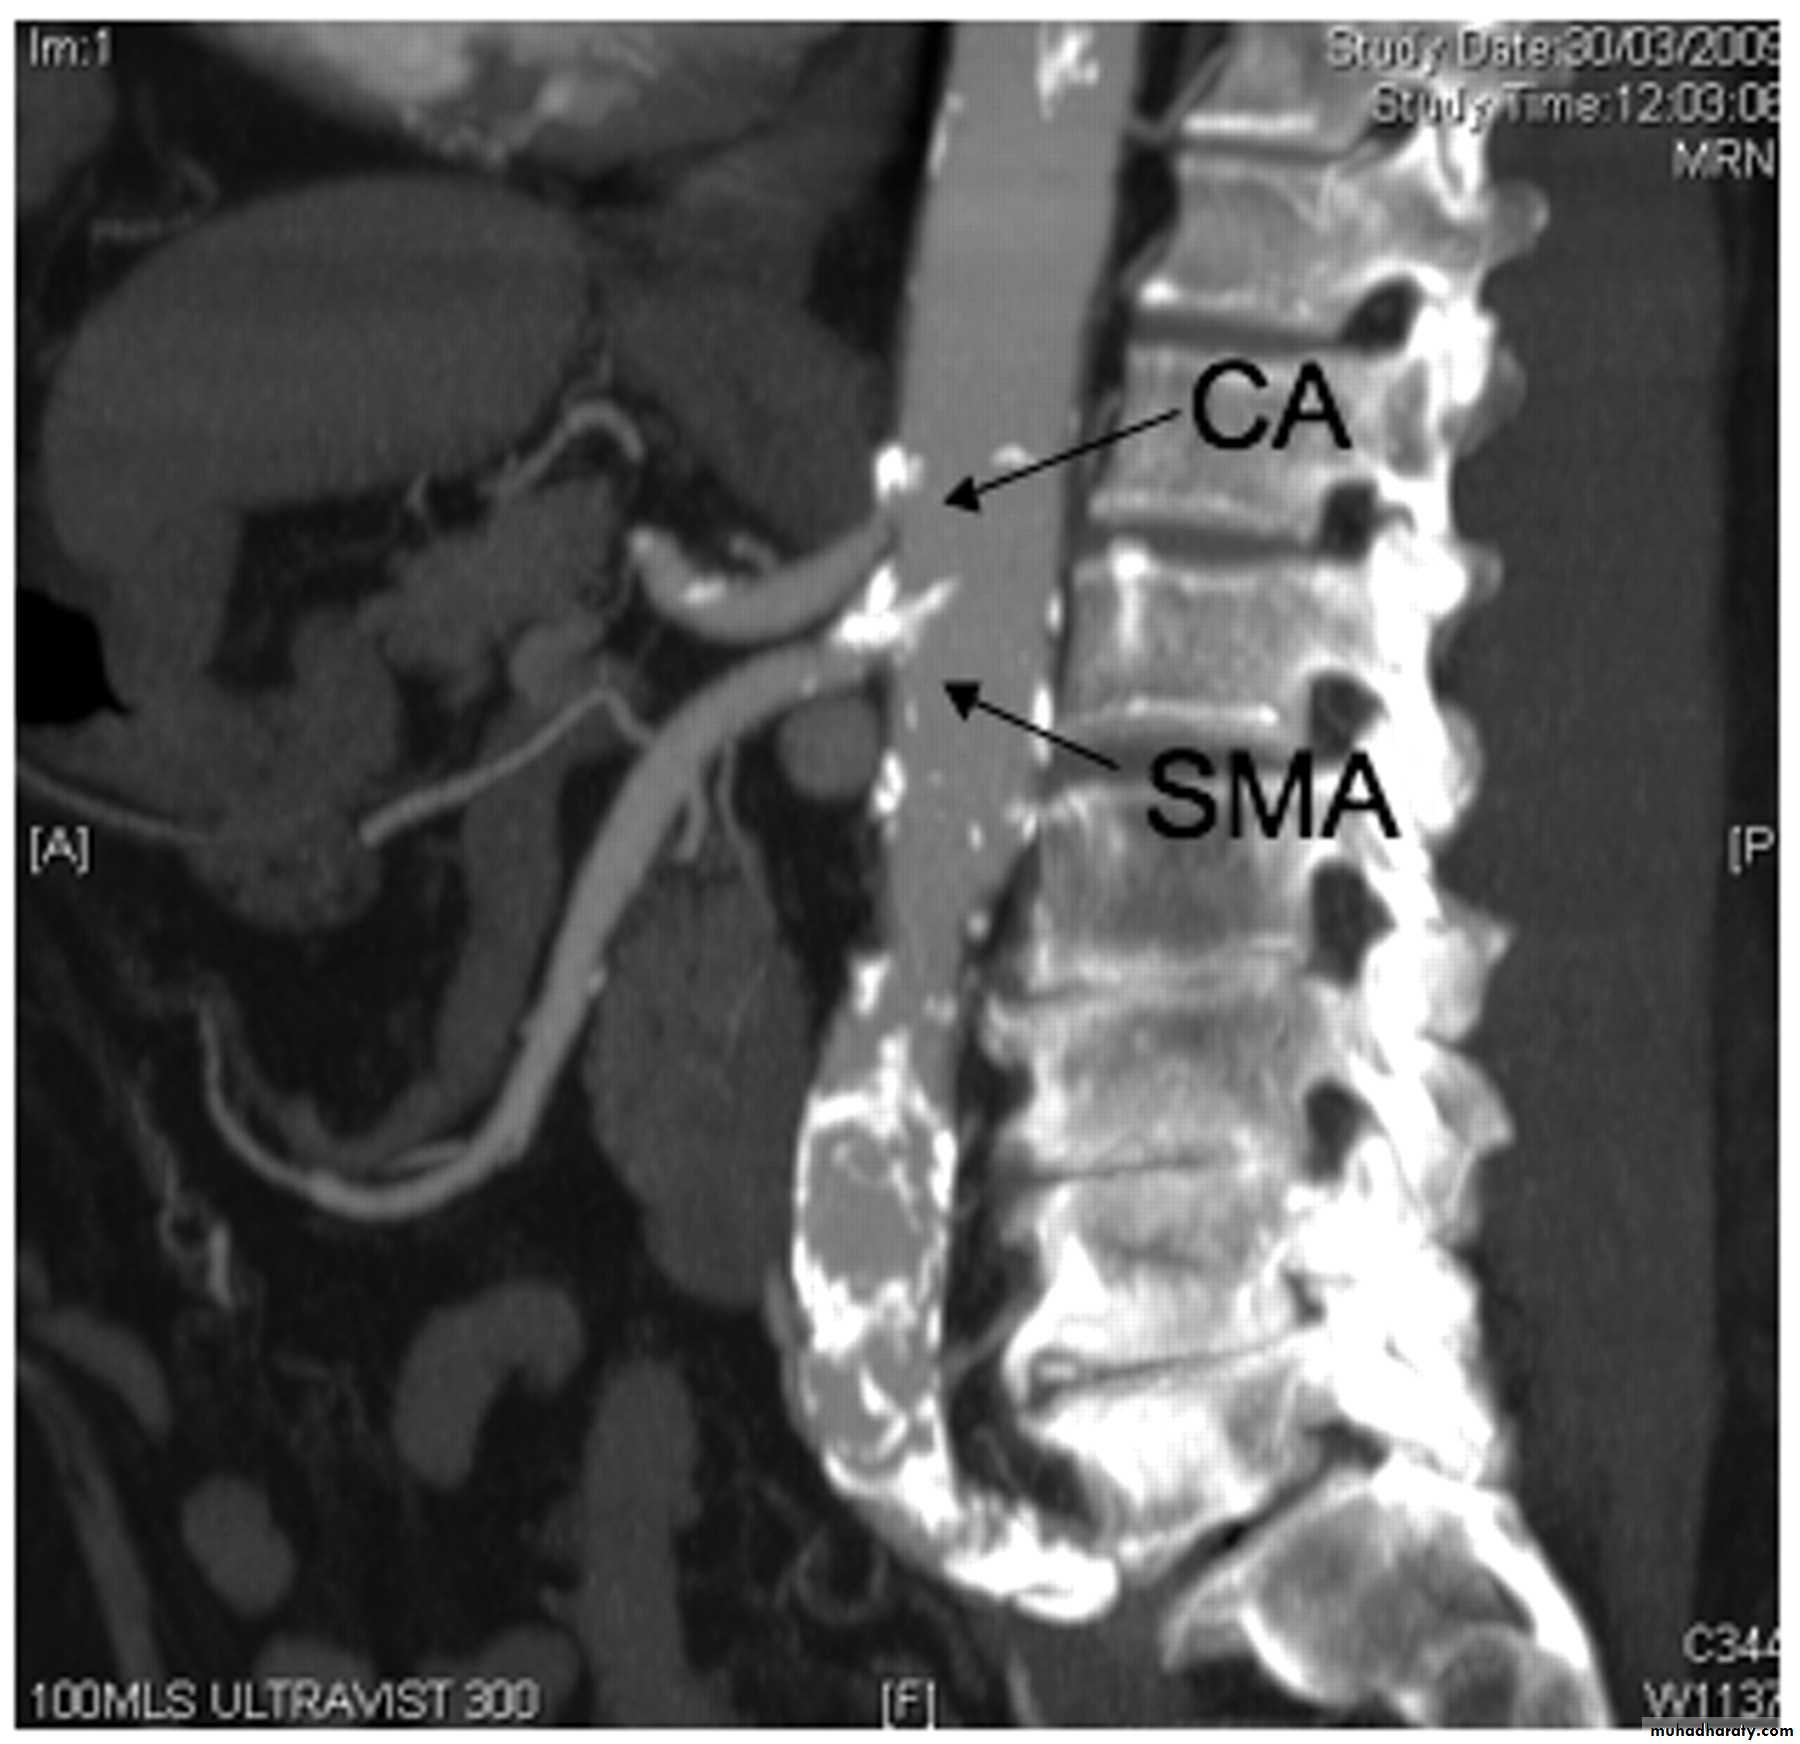

1- acute mesenteric ischemia (embolus or thrombus)2- chronic mesenteric ischemia.

Four distinct pathophysiologic mechanisms can lead to

acute mesenteric ischemia:

1. Arterial embolus(acute): most common, (left atrial(AF) or ventricular thrombi or valvular lesions), occlude the superior mesenteric artery(mid , distal).

2. Arterial thrombosis(acute or chronic): (proximal) mesenteric arteries.

CTA and MRA

Mesenteric arteriography

(definitive diagnosis)

Surgery: SMA bypass graft may originate from either the aorta or iliac arteryChronic Mesenteric Ischemia.

Endovascular Balloon dilatation or stent placement

Surgical: transaortic endarterectomy or mesenteric artery bypass.

Acute Thrombotic Mesenteric Ischemia